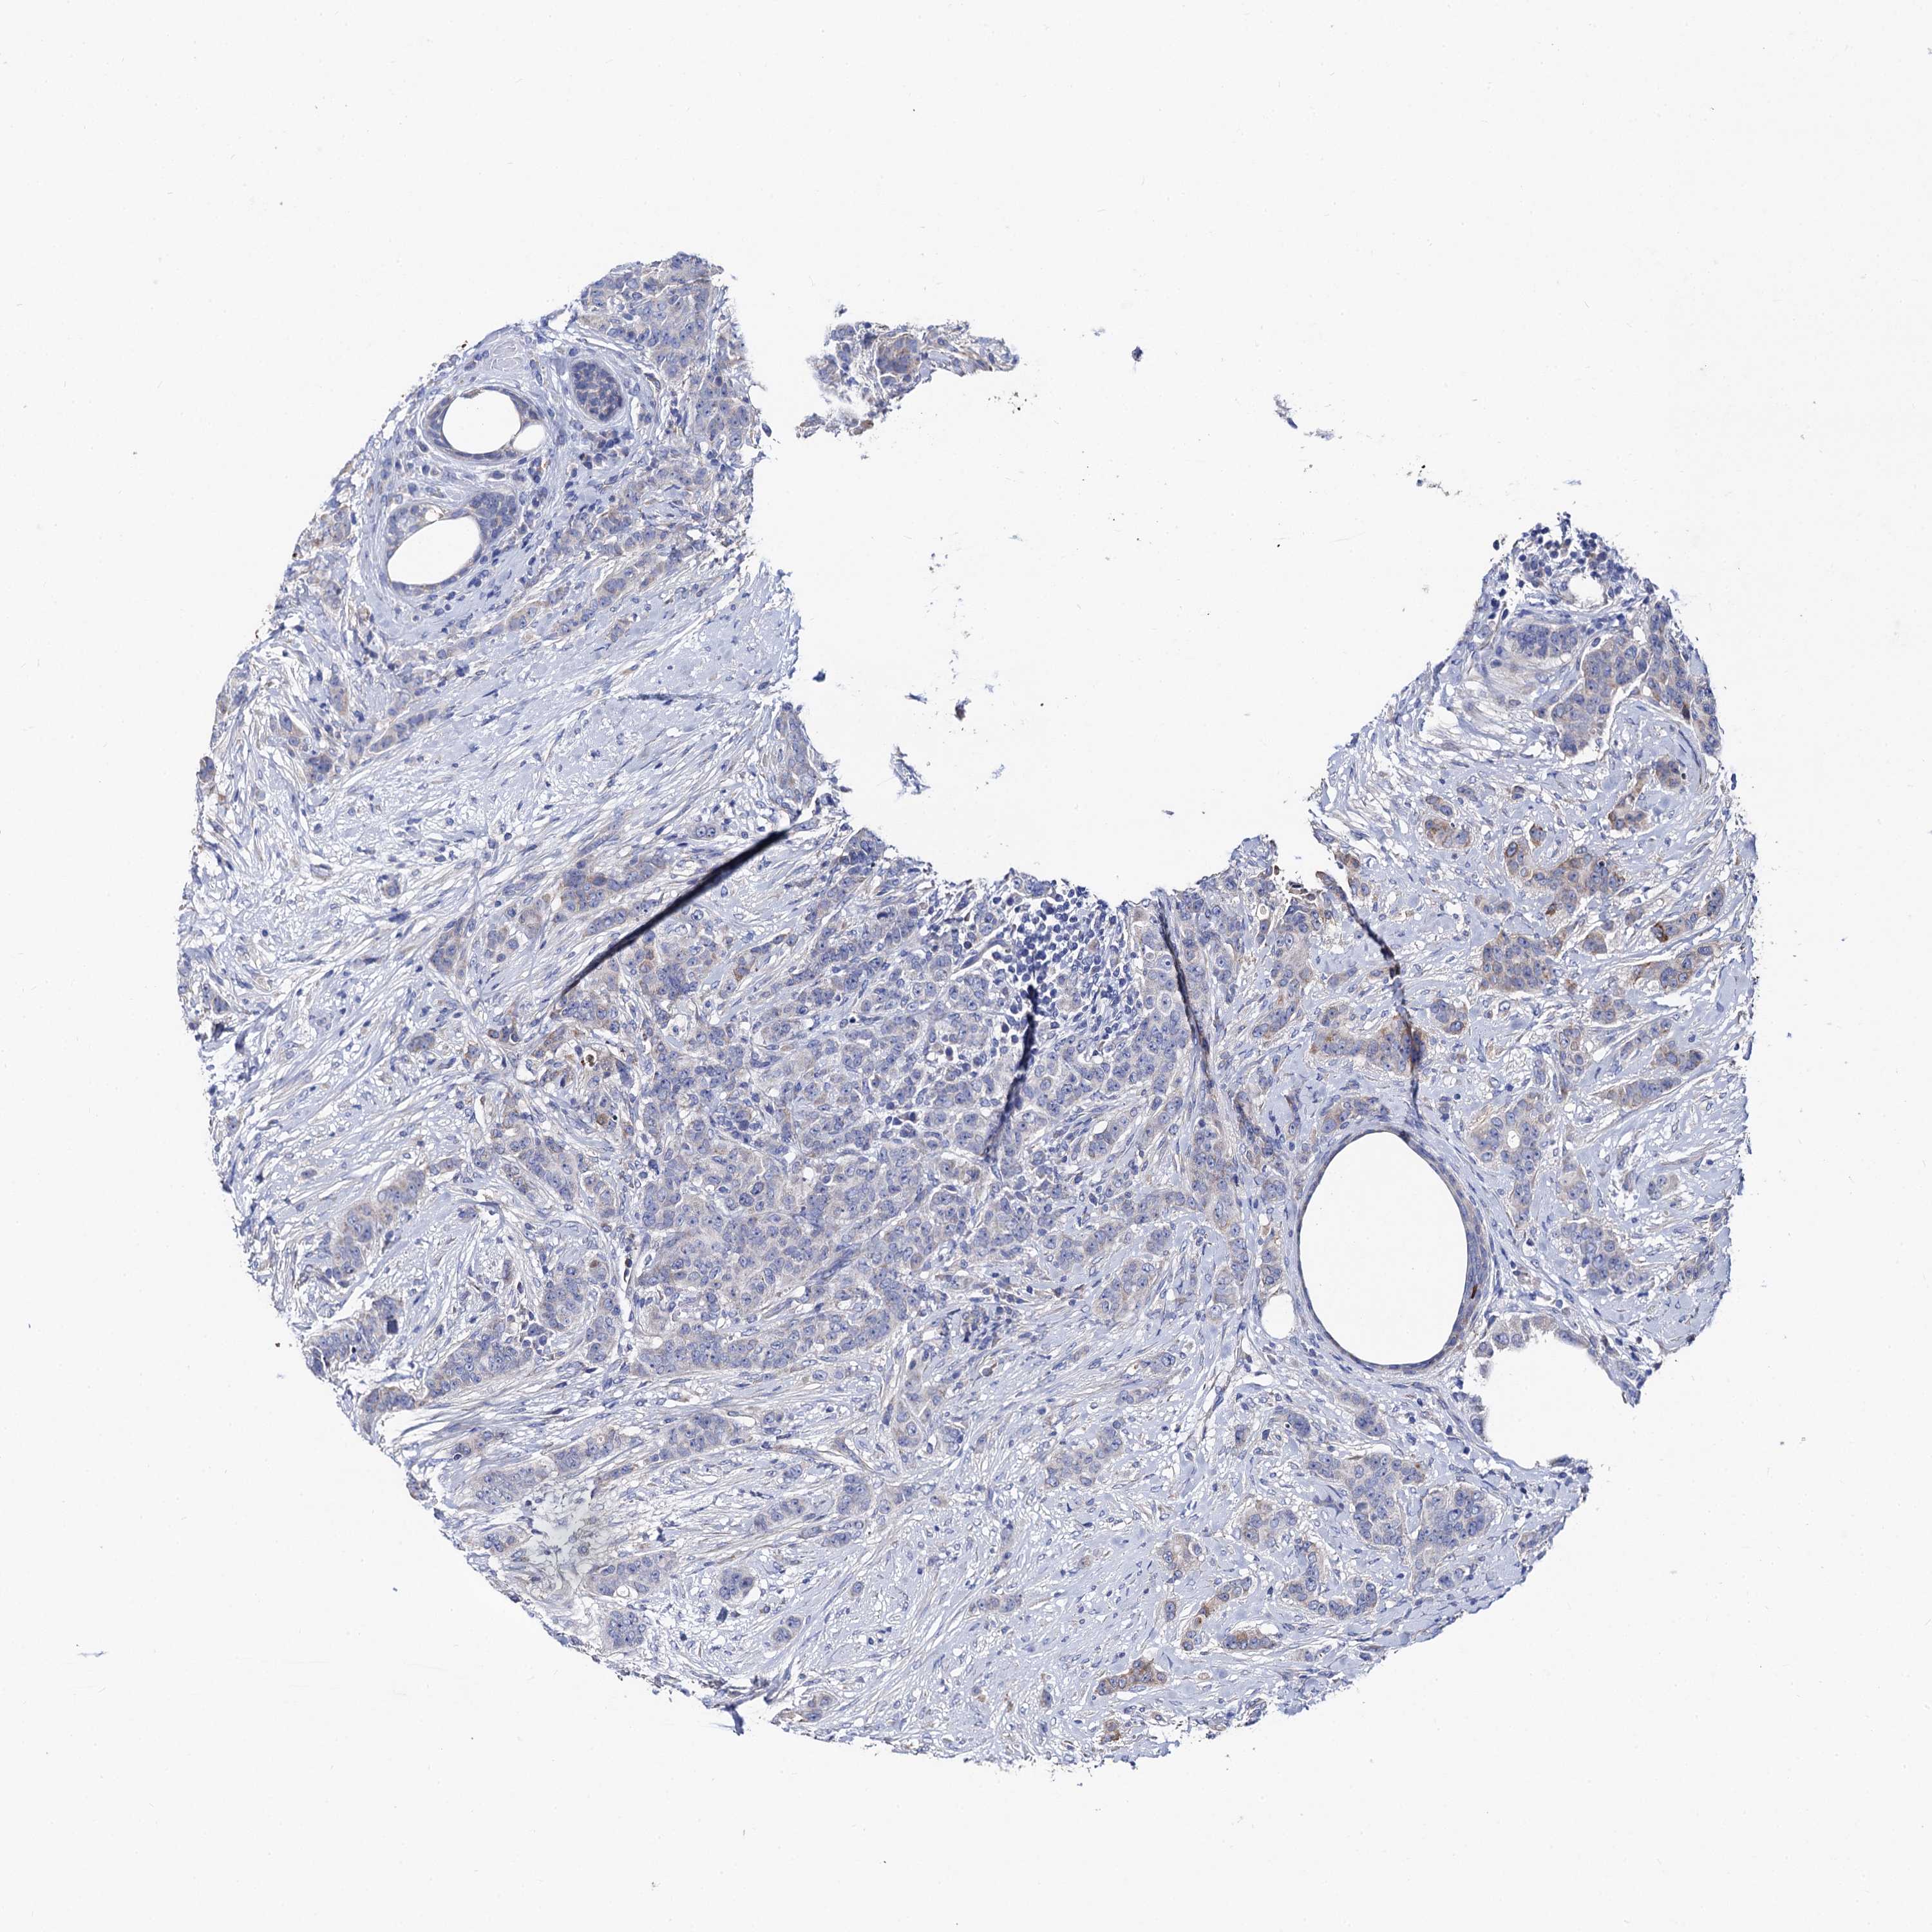

CANCER BREAST CANCER Show tissue menu

BRCA TCGA BRCA VALIDATION PROTEIN EXPRESSION